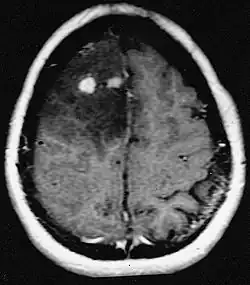

Die Patienten leiden an einer Vielzahl charakteristischer Symptome einer fokalen oder multifokalen massiven Läsion. Das Kernspintomogramm zeigt normalerweise Tumoren mit homogener Kontrastverstärkung innerhalb der tiefen periventrikulären weißen Substanz. Multifokalität und inhomogene Verstärkung sind typisch für Patienten mit geschwächtem Immunsystem. Extrem wichtig ist die Analyse des ZNS-Lymphoms bei der Differentialdiagnose von Hirnneoplasien. Es sollte beachtet werden, dass die Verabreichung von Kortikosteroiden zum vollständigen Verschwinden der Verstärkung führen kann, was Diagnose der Läsionen erschwert. Wenn das ZNS-Lymphom in der Differentialdiagnose berücksichtigt werden soll, sollten folglich Kortikosteroide vermieden werden, es sei denn, der Masseneffekt verursacht ein ernstes und unmittelbares Problem beim Patienten.

Hirnmetastasen sind die häufigsten intrakraniellen Neoplasien bei Erwachsenen, die zehnmal häufiger vorkommen als primäre Hirntumoren. Sie treten bei 20 bis 40 Prozent der krebskranken Erwachsenen auf und sind hauptsächlich mit Lungen- und Brustkrebs sowie Melanomen assoziiert. Diese Läsionen sind das Ergebnis der Ausbreitung von Krebszellen durch den Blutkreislauf und treten am häufigsten an der Verbindung der grauen mit der weißen Substanz auf, wo sich der Querschnitt der Blutgefäße ändert und damit Tumorzellembolien eingeschlossen werden. 80 Prozent der Läsionen treten in den Gehirnhälften auf, 15 Prozent im Kleinhirn und 5 Prozent im Hirnstamm. Ungefähr 80 Prozent der Patienten haben eine Anamnese von systemischem Krebs und 70 Prozent haben multiple Hirnmetastasen.

Bei Diagnose und Behandlung dieser Läsionen wurden in jüngster Zeit erhebliche Fortschritte erzielt, wodurch das Überleben und die Kontrolle der Symptomatik verbessert wurden. Das Auftreten von Anzeichen und Symptomen ähnelt denen anderer massiver Läsionen im Gehirn. Das Diagnoseverfahren der Wahl ist die Kernspintomographie unter Verwendung von Kontrastmitteln.